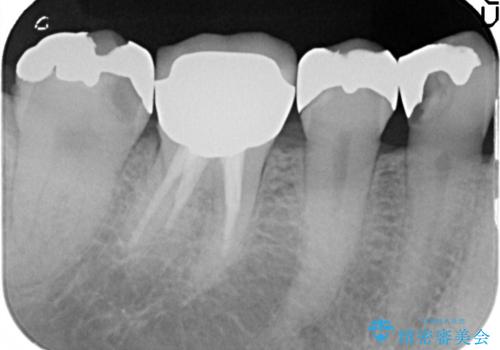

X線検査により、ゴールド修復下に虫歯の再発を多数認めました。

外から見てもわからない虫歯が修復物の下で密かに進行していることがあります。

定期的なX線検査を行うことにより早期発見をすることができます。